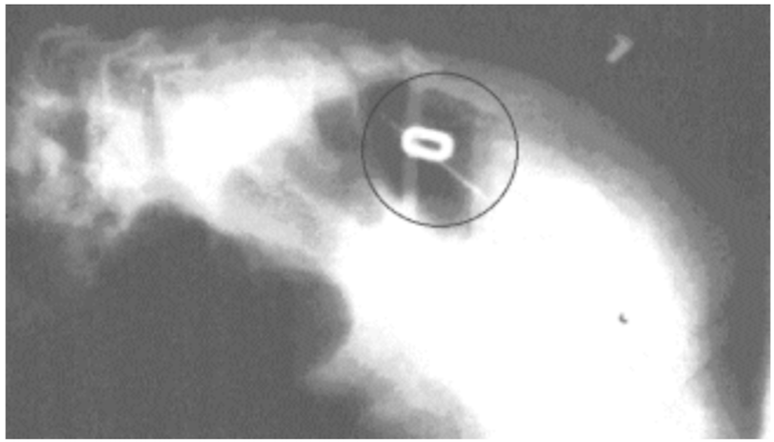

Radiografia feita do primeiro paciente, antes do procedimento cirúrgico. Após nossa análise, dois marcadores, em forma de 0 e 1, foram fixados sobre a pele da criança. O marcador Fonte: acervo pessoal.